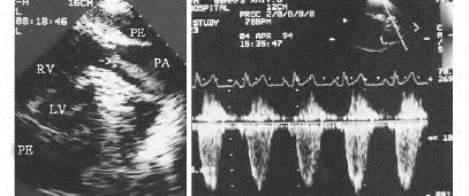

(1)彩色多普勒:显示收缩期经肺动脉瓣口的彩色血流束变细,呈多彩镶嵌的喷射状湍流,起自肺动脉瓣口射向肺动脉远侧(图16-12)。

图16-12 肺动脉瓣狭窄二维与彩色多普勒图(见彩图22)

左图示收缩期一束彩色血流(→)经肺动脉瓣口入肺动脉(PA)内,血流束变细,右图示收缩期湍流频谱

(2)脉冲多普勒:于肺动脉内取样显示收缩期负向湍流频谱,流速增快可持续整个收缩期。